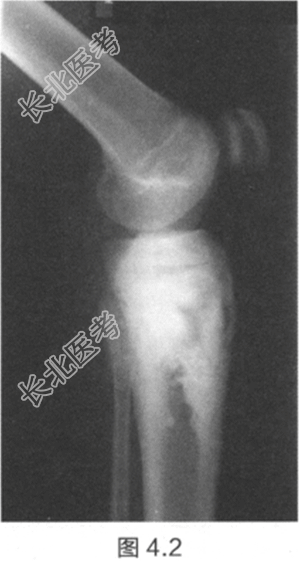

- [材料题] 一名15岁男孩,在度假做日光浴期间,父亲帮忙涂防晒霜时意外发现其小腿上端有肿块。肿块已经出现6个月,并且近期逐渐增大。检查:胫骨近端有一个坚硬、不规则、有压痛的肿块。肿块无疼痛,不影响膝关节活动,其他部位未见肿块。膝关节X线片见图4.1和图4.2。红细胞沉降率(ESR)和血清碱性磷酸酶升高。

- 简答题2、描述一下X线片特征。